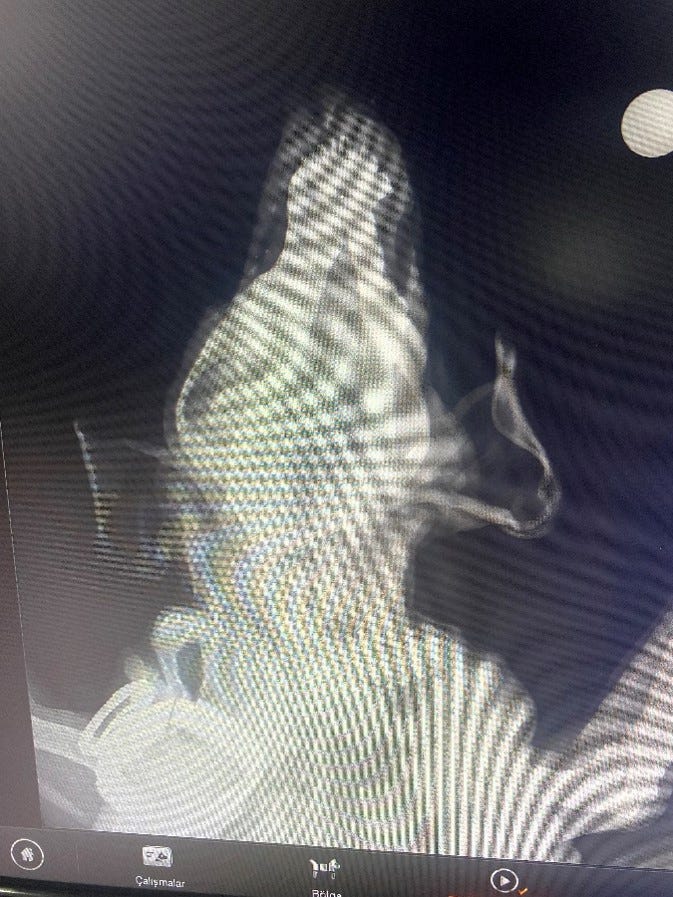

When x-rayed, Pamuk was found to have a number of bullets lodged in his body.

However, lead poisoning from the bullets would not cause the orbital & nasal discharge

Pamuk's X-rays indicated some irregularities that necessitated further examination. Upon reviewing the images, the medical team noticed areas that were not consistent with a typical, healthy scan.

These abnormalities prompted our vets to recommend additional tests to determine the underlying cause.

Later, he returned inside where a surgical dye was applied to enhance imaging. This dye helped in obtaining clearer, more detailed images during the second set of X-ray pictures, which were crucial for his diagnosis and subsequent treatment plan.